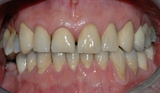

Bildet viser et eksempel på moderat tannslitasje som følge av tanngnissing.

Slitasjen er spesielt tydelig i overkjeven.